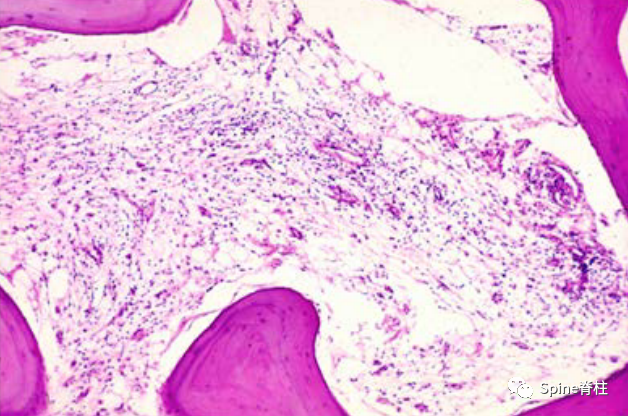

- Modic 等人的第二篇论文回顾了 474 例腰椎成像患者的 MRI。该研究注意到在与椎间盘退行性变有关的终板周围软骨下骨髓中存在两种类型的信号强度变化,MC-1 和 MC-2。该研究包括对 16 名患者进行一到三年的重复 MRI 随访。此外,还对 6 名因椎间盘疾病接受腰椎手术的患者进行了椎间盘-终板-椎体交界处的组织病理学分析,如图 1-3。MC-1 或 MC-2 的骨髓信号变化仅在存在相邻椎间盘退变的情况下发现。在 14 至 36 个月的随访中,六分之五的患者从 MC-1 转变为 MC-2。在 6-12 周内,凝乳蛋白酶注射(Chymopapain injection)会诱导 MC-1 变化和进一步的椎间盘退变。重要的是,该研究得出的结论是,MC-1 可能被解释为对椎间盘退变时椎体骨髓所承受的损伤的急性至亚急性修复反应。而 MC-2 代表更稳定的状态,随着时间的推移没有显著的转换。该研究进一步强调了这些发现与椎间盘退变相关的临床重要性;可与继发于恶性肿瘤或骨髓炎的变化区分开来。

图 1. 终板-椎体交界处的 H&E 染色显示正常组织与椎骨内的造血成分和骨小梁。

图 2. 具有纤维血管成分和增厚的骨小梁的 MC-1 的组织学 H&E 染色

图3.MC-2组织学H&E染色,骨髓间隙脂肪替代,在T1加权图像上显示高信号